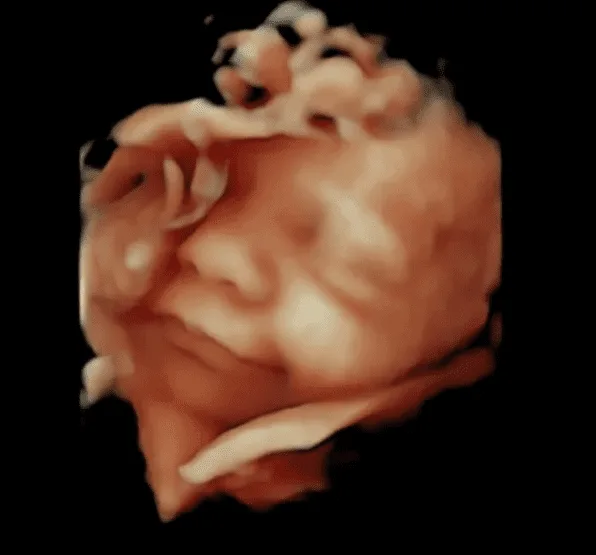

Échographie 4D

Une échographie en 3D ou 4D se déroule de la même façon qu’une échographie normale. Les images en 4D seront faites pendant l’échographie de suivi de la grossesse. « Il existe trois échographies obligatoires pour la femme enceinte : la première aux alentours de 10 semaines de grossesse, pour détecter une éventuelle trisomie, la deuxième autour de 20 à 22 semaines, pour vérifier l’absence d’anomalies chez le fœtus et voir sa morphologie, et la troisième, vers 30 à 32 semaines de grossesse, pour voir la position du bébé et détailler sa croissance »